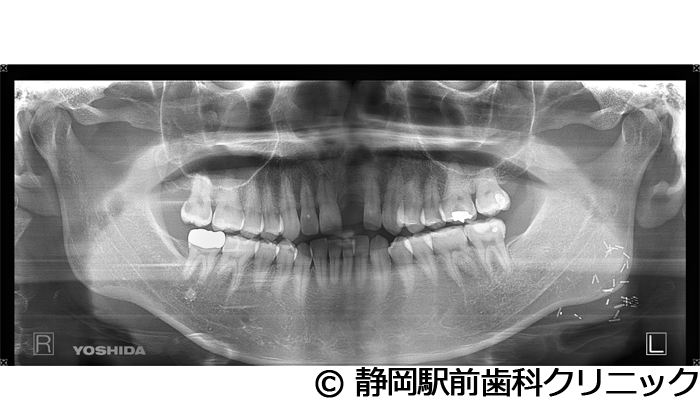

【症例1】左上インプラント埋入

- 治療前

- 治療後

- 治療名

- 左上インプラント埋入

- 費用

- 330,000円(税込)

- 期間

- 6ヵ月

治療内容

患者様の症状

左上の歯が歯根破折で、被せ物が土台から取れてしまった。インプラント治療希望。

治療方法

残った歯の抜歯を行い、骨の治癒後にCTを撮影。精密に診断後、インプラントを埋入した。ソケットリフトを併用し、インプラントの埋入範囲も確保しながら行った。その後、人工歯を被せて咬合と審美の両方を構築した。

治療結果

術後はほぼ痛みがなく、短期間で噛むことができるようになったとご満足いただけました。見た目も自分の歯のようだと喜んでいただけました。

※治療結果は個人差があります。

治療を行う上での注意点(リスク・副作用)

術後は、出血、腫れ、痛みなどが出る可能性があります。